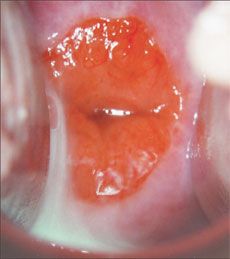

Fifteen-year-old Melanie comes to see your associate in the office for a "routine" pelvic examination. She has been sexually active with 1 partner for the past year. She swears that she always uses condoms during sexual intercourse and has never had any problems with a condom breaking. Melanie denies any symptoms of vaginal discharge, odor, or itching. On pelvic examination, your associate notices that Melanie's cervix appears erythematous and inflamed. She considers Chlamydia cervicitis, which causes cervical friability, as a possible diagnosis. Melanie restates that she has been asymptomatic and has taken every precaution to protect herself from getting an STD. She asks your associate to get a second opinion. At your associate's request, you take a look at Melanie's cervix.

This is

cervical ectropion

--a common, nonpathologic finding in adolescents. Remember that the normal female cervix typically consists of squamous epithelial cells on the exocervix with columnar epithelial cells lining the endocervix. The cervical transformation zone represents the area in which the squamous and columnar epithelial cells meet. In most mature women, this transformation zone occurs well within the cervical os. The cervix of young adolescents (and pregnant women) often demonstrates ectropion, in which the columnar cells and transformation zone actually extend onto the exocervix. These cells appear deep red in contrast with the pink squamous epithelial cells. While this can be a normal physical finding, the presence of the columnar cells on the exocervix places adolescents at higher risk for contracting infection with

N gonorrhoeae

or

Chlamydia.

Culture specimens are mandatory during a routine pelvic examination. However, many clinicians would not prescribe antibiotics unless the cultures demonstrated infectious growth.